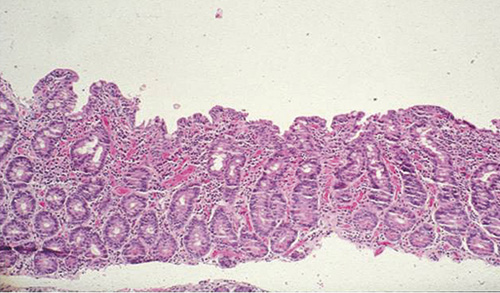

Celiaki orsakas av proteinet gluten i vete, råg och korn som initierar en inflammation, vilken slutligen leder till villusatrofi av tunntarmens slemhinna (Figur 1).

År 1888 rapporterades de första kliniska fallen av barn med celiaki. Först ett halvt sekel senare visade barnläkaren Dicke på kopplingen mellan celiaki och intag av gluten från vetemjöl [1]. När tunntarmskapslarna utvecklades på 1950-talet kunde biopsier från slemhinnan undersökas och typiska histologiska förändringar påvisades. Dessa förändringar normaliserades vid behandling med glutenfri kost [2] (Figur 1).

Figur 1. Dissektionsmikroskopisk bild från frisk slemhinna (överst) och från atrofisk slemhinna (under). Histologisk bild av normal duodenalslemhinna (tredje uppifrån) och av total villusatrofi (nederst).